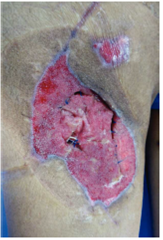

A principios de los 90´s Argenta y Morykwas introdujeron la terapia de presión negativa con la primera publicación en 199712,13, está ha sido la mayor innovación en el manejo de heridas. El dispositivo consiste en un adhesivo con un tubo conectado a un recipiente de recolección y una fuente de vacio. El material de interfaz es una esponja de poliuretano de poro abierto, hidrófobo que tiene que sellar adecuadamente para mantener el vacio o el aire se fuga causando desecación, otros materiales que se utilizan son esponjas con alcohol polivinílico, o gasas. Estos, deben actuar como una interfaz para distribuir el vacio a lo largo de la herida y permitir que se eliminen los fluidos.13 La presión negativa que se aplica puede ser constante o intermitente, se recomienda una presión de 125 mmHg, pero puede aumentarse hasta 175 mmHg.14 Requiere de cambios cada 48 a 72 horas (fig. 1 ).

Figura 2 Paciente masculino de 23 años de edad con herida por arma de fuego en miembro pélvico derecho

Figura 3 Mismo paciente manejado con desbridamiento quirurgico, terapia V.A.C.® durante 2 semanas y posteriormente aplicación de Alloderm®